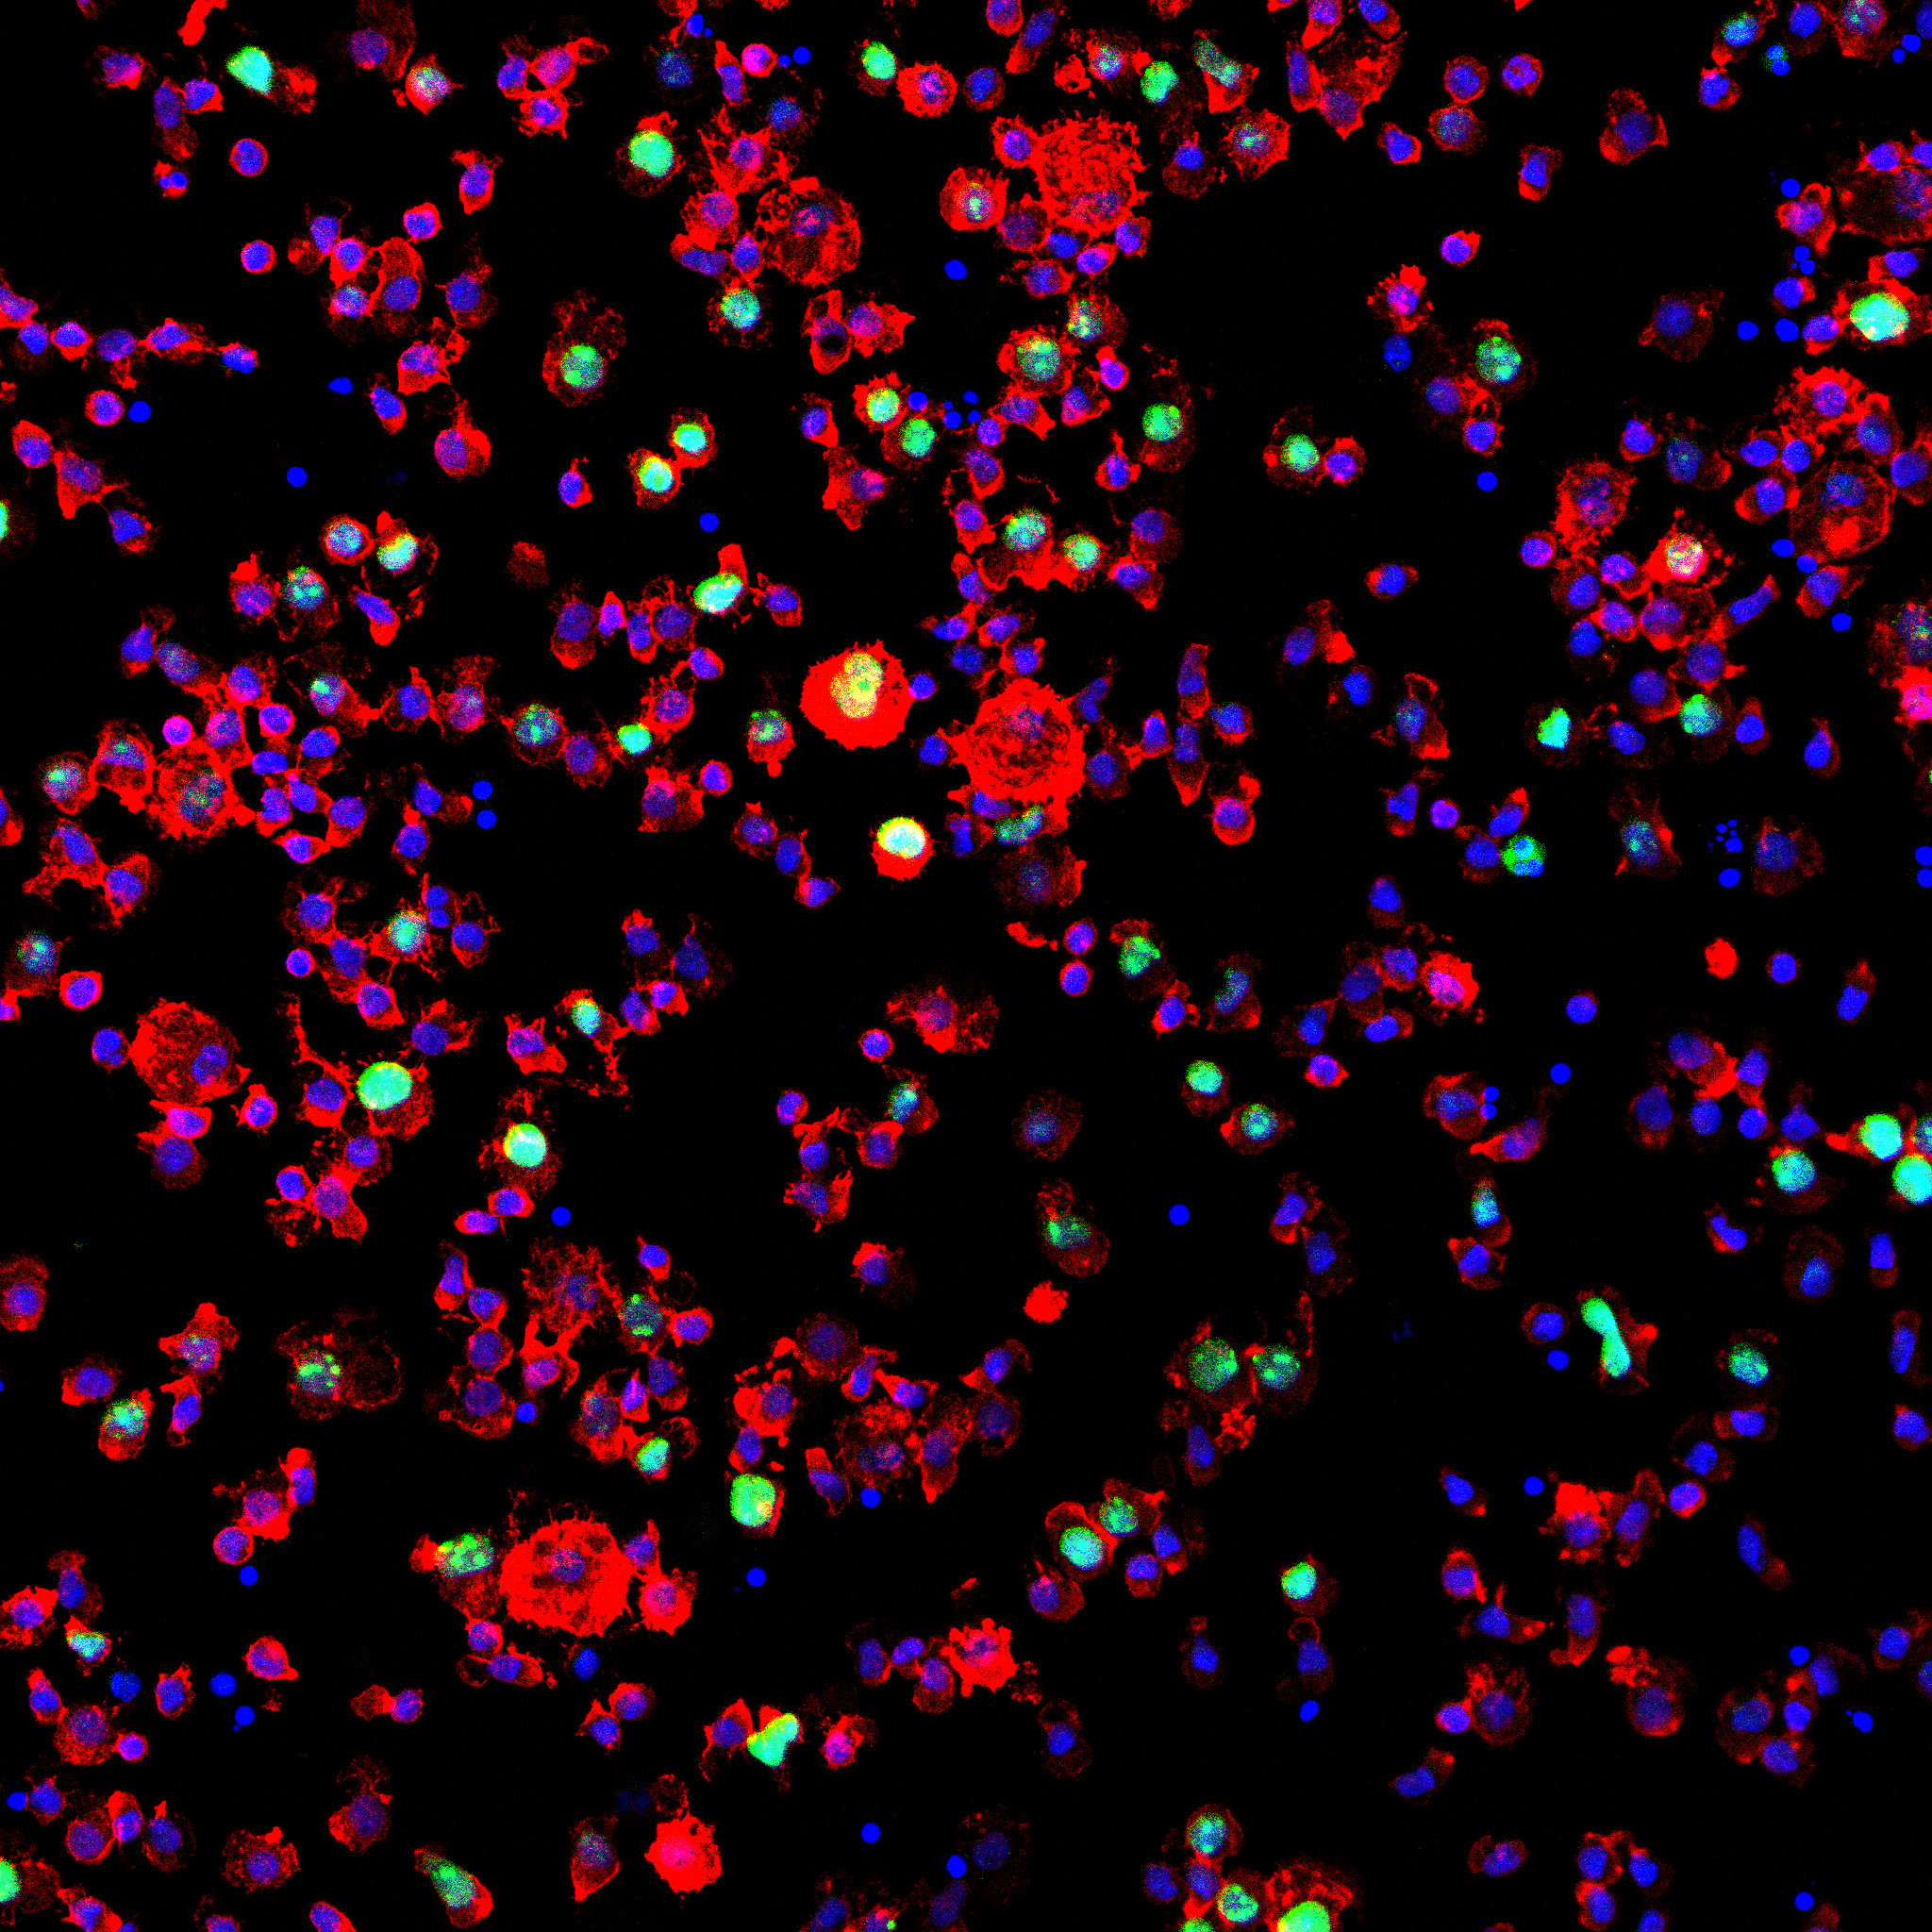

Zarejestrowane pod mikroskopem konfokalnym przez naukowców: dr hab. n. med. Tomasza Cichonia i dr n. med. Ryszarda Smolarczyka obrazy komórek nowotworowych posłużyły jako punkt wyjścia do stworzenia dzieł sztuki. Zdjęcia powstały przy wsparciu dr hab. n. med. Tomasza Rutkowskiego. Każde ze zdjęć zostało umieszczone na płótnie jako „baza” do obrazu. Następnie polski artysta – Paweł SWANSKI namalował na nich struktury walczące z komórkami nowotworu.

Wszystkie powstałe w ten sposób obrazy, jak i cały performance, zostały zarejestrowane i zamienione w kolekcje NFT.